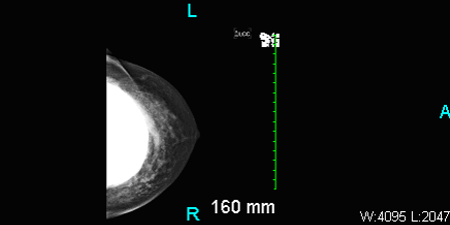

Aside from fever, other vital signs were normal. The patient had bilateral palpable sub-glandular silicone implants with Baker Grade 3 capsular contracture (ie, breast firm to the touch with visible breast deformity) of the right breast. There were no masses and no axillary lymphadenopathy. The right breast was swollen, erythematous, and tender, with an intact inframammary scar. Results of ultrasonography showed no fluid collection or abscess.

Breast augmentation with implants also can make mammography challenging.10 Additional ultrasonographic images are usually needed to detect pathology. But, as seen in this case, implant material may effectively obscure a lesion.

Figure: Ultrasound of right breast showing subglandular implants. No definite abscess seen.